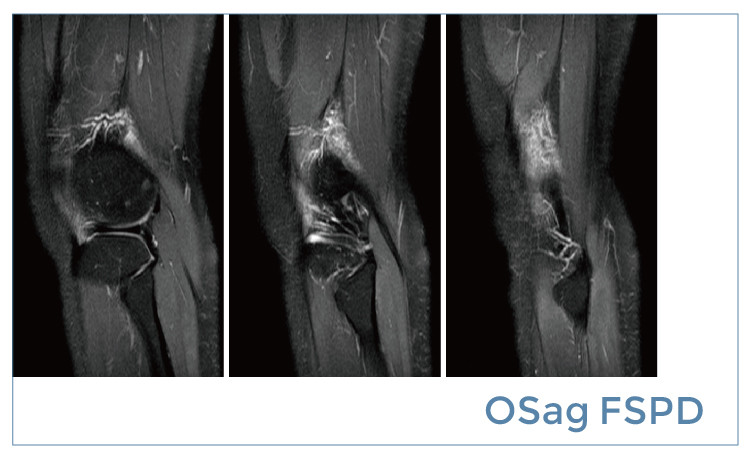

【朗润影像档案】磁共振影像病例分享(编号20190510)